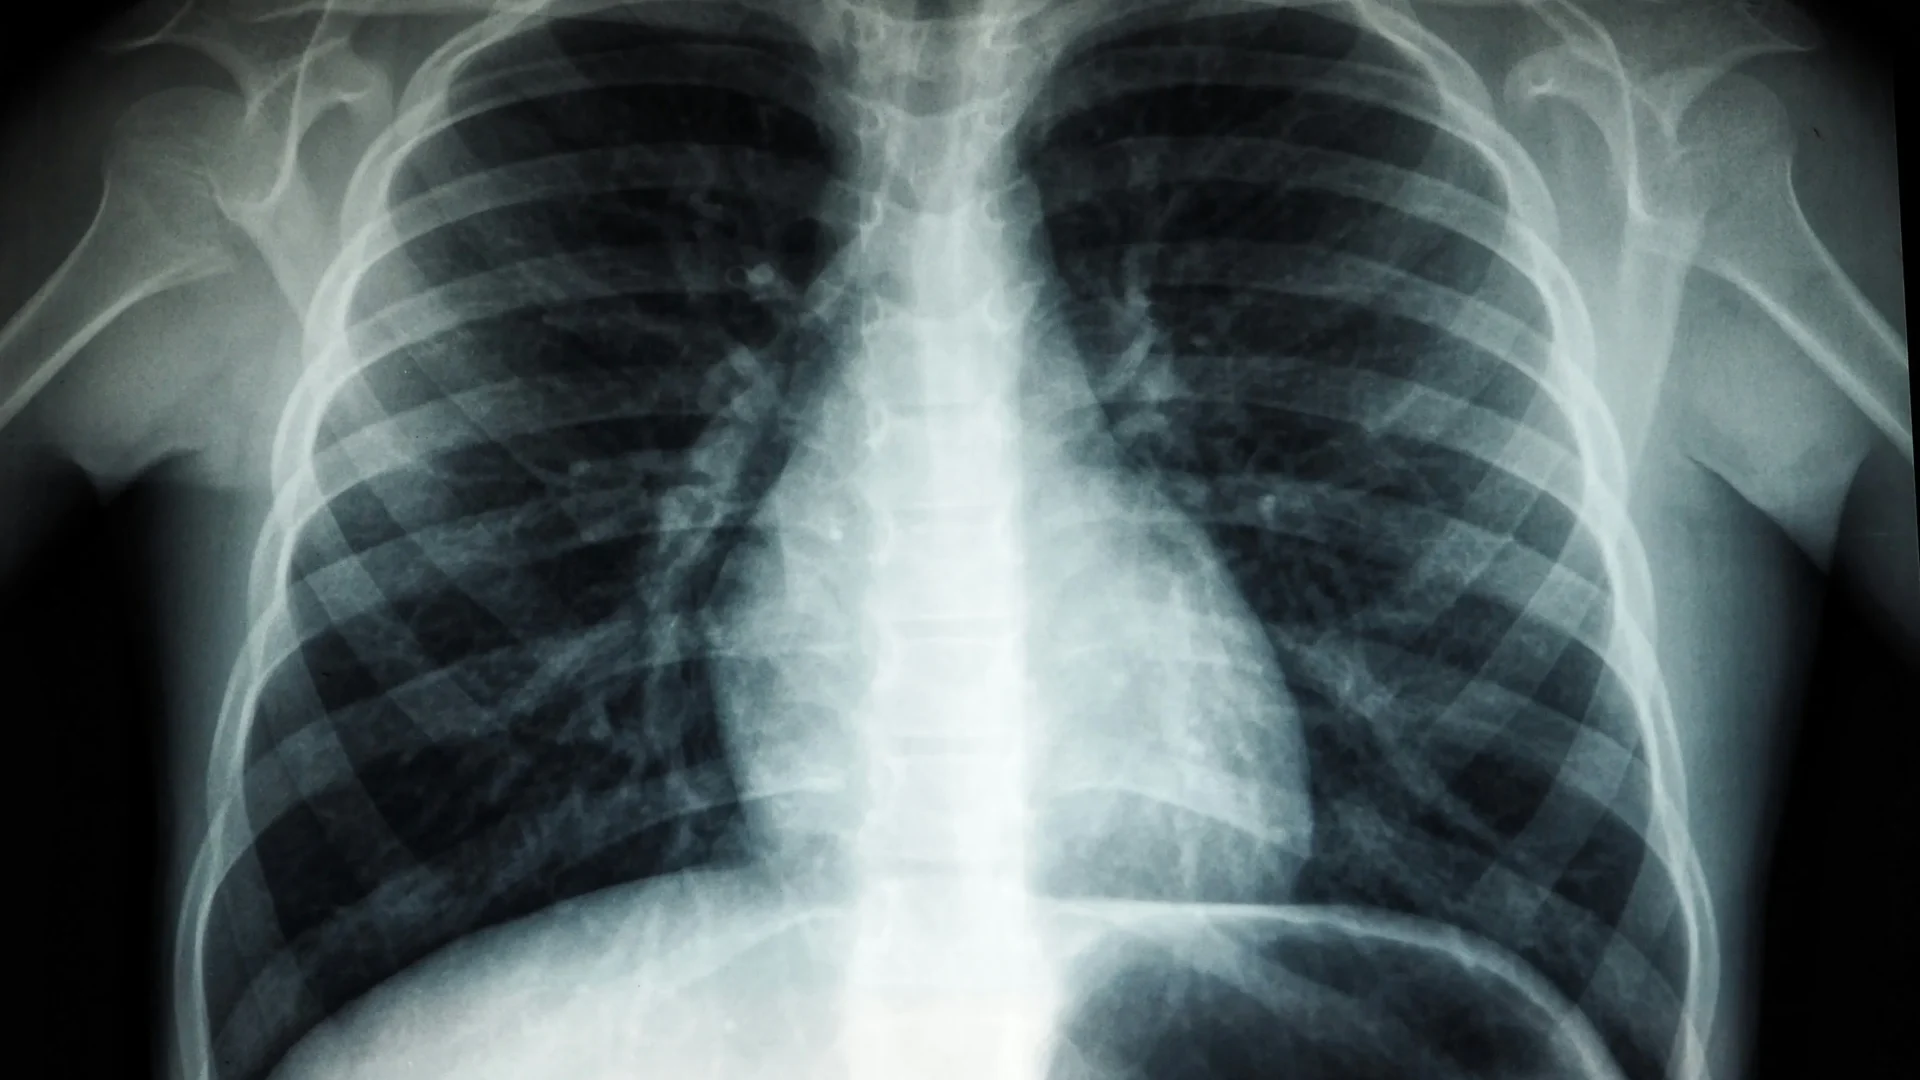

Bildgebende Verfahren wie Röntgen und Computertomografie (CT) gehören zu den wichtigsten diagnostischen Methoden der modernen Medizin. Sie ermöglichen einen präzisen Blick in den Körper, helfen bei der Früherkennung von Erkrankungen und unterstützen Ärztinnen und Ärzte bei der Planung von Therapien. Da diese Verfahren jedoch ionisierende Strahlung einsetzen, ist der Strahlenschutz ein zentrales Thema – zum Schutz von Patientinnen, Patienten und medizinischem Personal.

Röntgenstrahlen können Zellen schädigen, wenn sie in hoher Dosis auf den Körper treffen. Auch wenn moderne Geräte die Strahlenmenge deutlich reduzieren, gilt das Prinzip: So viel wie nötig, so wenig wie möglich. Strahlenschutz bedeutet, die Belastung so weit zu verringern, dass ein qualitativ hochwertiges Bild entsteht, ohne unnötige Exposition zu verursachen. Das schützt Menschen, die untersucht werden, und auch die Fachkräfte, die regelmäßig mit den Geräten arbeiten.